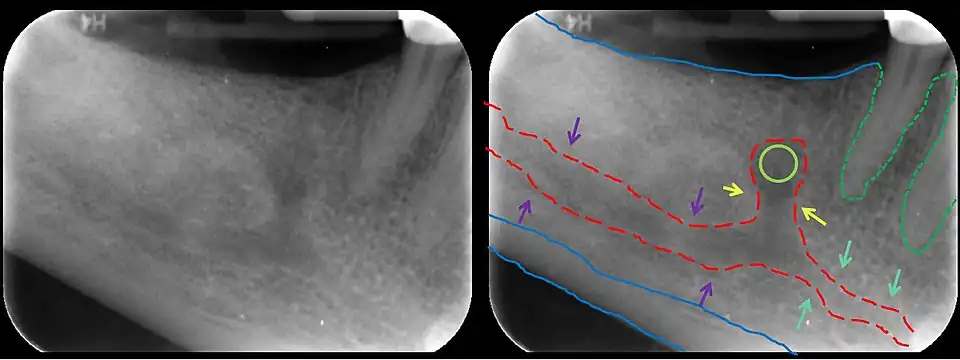

In human anatomy, the mandibular canal is a canal within the mandible that contains the inferior alveolar nerve, inferior alveolar artery, and inferior alveolar vein. It runs obliquely downward and forward in the ramus, and then horizontally forward in the body, where it is placed under the alveoli and communicates with them by small openings.

The mandibular canal is continuous with two foramina: the mental foramen which opens in the mental region of the mandible and carried the distal fibres of the inferior alveolar nerve as the mental nerve; and the mandibular foramen on medial aspect of ramus, into which the mandibular nerve enters to become the inferior alveolar nerve. The mandibular canal often runs close to the apices of the third molar tooth, and the inferior alveolar nerve can become damaged during removal of this tooth, causing sensory disturbance in the distribution of the nerve. This is sometimes the case for the second or first molar teeth, and care must be taken during removal or root canal treatment in such cases to prevent nerve injury or extrusion of root canal filling materials.[2]

Variations

Several variations of the mandibular canal exist with varying frequency. The most common variant is the retromolar canal (~10 % of canals), whereby a branch is given off in the mandibular ramus which terminates in the retromolar region of the mandible. The retromolar canal may cause bleeding during surgery in the retromolar region such as removal of mandibular third molar teeth. Other variants include a bifid canal with a branch (~41%):[3] following the course of the main mandibular canal before re-joining it (forward or buccolingual type); terminating at the apex of a tooth, usually the molar teeth (dental type); opening as an accessory mental foramen.[4] A trifid mandibular canal variation has also been described.[5][6]